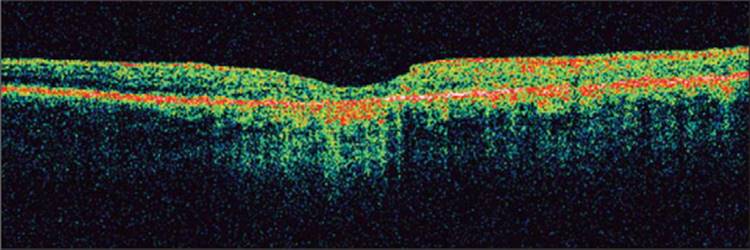

Mydriasis is not always necessary to obtain OCT but may provide a higher signal-to-noise ratio and consequently better microstructural details. Dilation also decreases the amount of 'vignetting' which is described below. Obtaining quality OCT images depends upon the light being able to reach the target tissue. If there is significant media opacification such as corneal opacification or severe cataract there will be less light reaching the posterior segment and less light returning to the inferometer for detection. This 'signal-to-noise ratio' is displayed on the screen and labeled as 'signal strength'. A signal strength of 10 represents the highest quality imaging whereas a signal strength of zero represents the lowest quality. If there is little light reaching the tissue, the images appear dull or 'washed out' and it is difficult to detect subtle abnormalities and differences in tissue reflectivity. Figure 130.4 shows an example of low signal strength. Notice how the ordinarily highly reflective structures appear blue or even black. Moderate media opacities such as early cataract, asteroid hyalosis, and mild vitreous hemorrhage do not preclude adequate imaging.[20,21] OCT can be performed through silicone oil, but not through intraocular gas.

Click to view full size figure

FIGURE 130.4 Example of low 'signal-to-noise ratio'. Notice how the entire image appears 'washed out'. It is difficult to discern details of the retinal microstructure. The signal strength is relatively low at three.